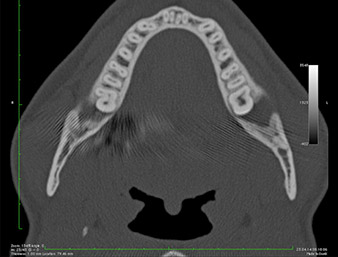

Ya en la ortopantomografía, se constató que había un resto radicular de la región 38 muy cerca del nervio alveolar inferior (figura 1). La raíz se había fracturado durante la osteotomía, pero el primer odontólogo que había tratado al paciente no había extraído esta debido a la presencia de dolor durante la operación.

Ortopantomografía

Imagen 1: Ortopantomografía 6 meses después de la osteotomía del diente 38: el resto radicular se encontraba cerca del nervio alveolar inferior.

La anamnesis del paciente era favorable (no fumador, 26 años) para garantizar el éxito de la aplicación. Como la ortopantomografía mostró que el resto radicular se encontraba muy cerca del nervio alveolar inferior, se realizó también una tomografía volumétrica digital (6).